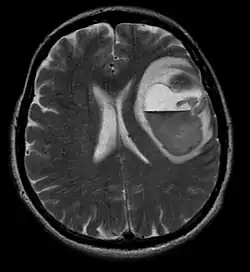

Meningeome sind die häufigsten intrakraniellen extrinsischen oder extraaxialen Hirntumoren, die aus den Zellen der Arachnoidea entstehen, der Membran, die das Gehirn und das Rückenmark bedeckt. Die Inzidenz dieser Neoplasie beträgt etwa 2 Fälle pro Jahr pro 100.000 Einwohner. Sie treten häufiger bei Frauen im sechsten und siebten Lebensjahrzehnt auf. Ihre Häufigkeit ist bei Patienten mit Typ-2-Neurofibromatose höher. Der Verlust des Chromosoms 22 ist charakteristisch für Meningeome, obwohl die prognostische Bedeutung dieses Befundes noch unklar ist.

Patienten mit Meningeom können Symptome aufweisen, die für eine massive Schädelläsion typisch sind, einschließlich Anfällen und fokalen neurologischen Defiziten.[35][36] Da Meningeom auch asymptomatisch sein können, werden sie manchmal bei Computer- und Kernspintomographien aus anderen Gründen entdeckt. Dieser Resonanztumor hat ein charakteristisches Erscheinungsbild, das normalerweise aus einer gleichmäßigen Kontrastverstärkung entlang der Dura mit klarer Trennung vom Gehirnparenchym besteht. Ein weiteres Merkmal, obwohl nicht in allen Fällen vorhanden, ist der sogenannte „Duralschwanz“, der durch eine Verstärkung dargestellt wird, die über die Läsion hinausgeht und den Verankerungspunkt in der Dura anzeigt.[37]

Viele zufällig entdeckte Meningeome müssen zum Zeitpunkt der Erstdiagnose nicht behandelt werden.[38] Wenn beim Patienten ein signifikanter Masseneffekt festgestellt wird, unabhängig davon, ob Symptome vorliegen oder nicht, ist die Behandlung der Wahl normalerweise eine vollständige Resektion. In einer Studio der Mayo-Kliniken, in der die Tumorkontrollraten nach chirurgischer Resektion und Radiochirurgie bei Patienten mit kleinem bis mittlerem intrakraniellem Meningeom und ohne Masseneffektsymptome verglichen wurden,[39] führte die Radiochirurgie zu einer besseren Kontrolle (98 gegenüber 88 Prozent) und mit weniger Komplikationen (10 gegenüber 22 Prozent) im Vergleich zur chirurgischen Entfernung.